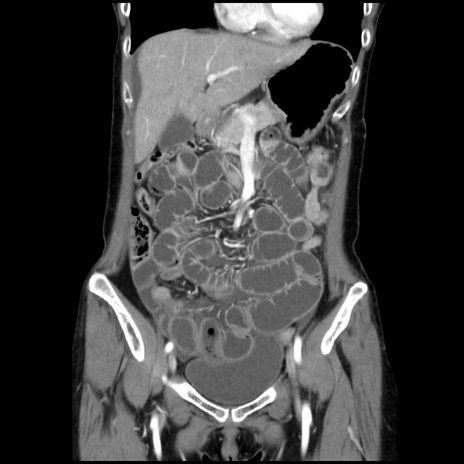

横断像

【症例】40歳代 女性

【主訴】上腹部痛、嘔気・嘔吐

【現病歴】約9時間前頃から急に上腹部痛、嘔気、嘔吐が出現。改善しないため救急要請。

【既往歴】子宮頚癌(広汎子宮全摘術、放射線療法)、腸閉塞

【身体所見】腹部:平坦、軟、腸雑音亢進、上腹部を中心に腹部全体に圧痛あり。

【データ】WBC 8400、CRP 0.03